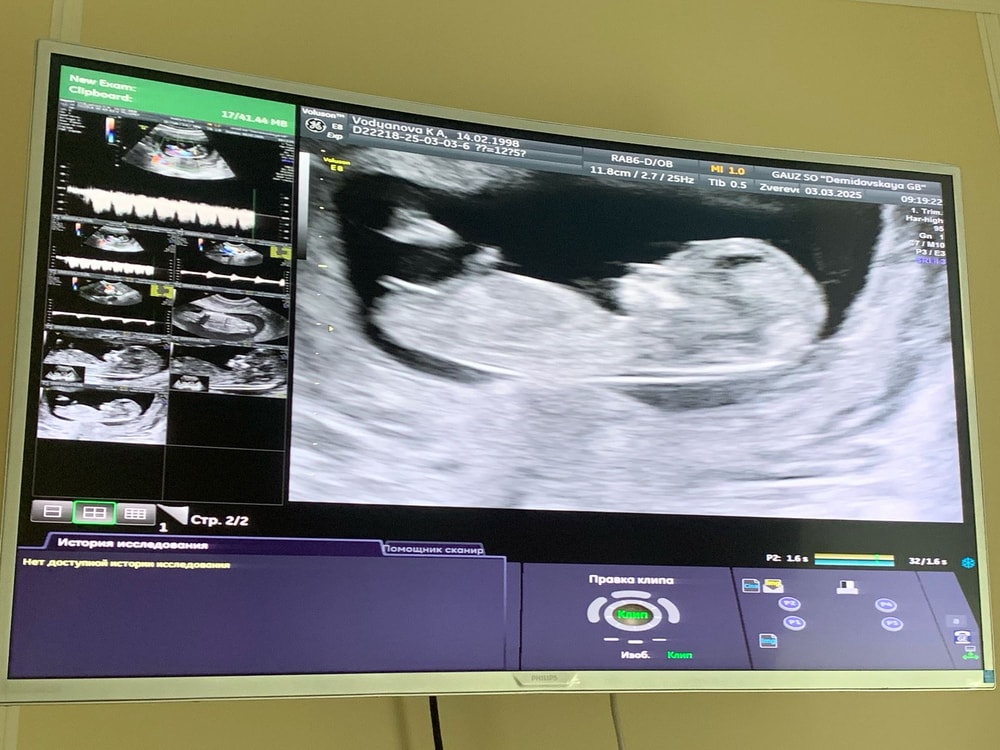

Размеры плодного яйца на 5 Неделе 4 дня 3D узи Краснодар